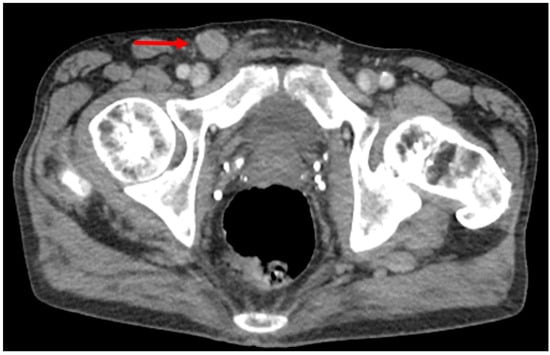

3. Computed Tomography

3.1. Primary Staging

3.2. Restaging and Post-Treatment Surveillance